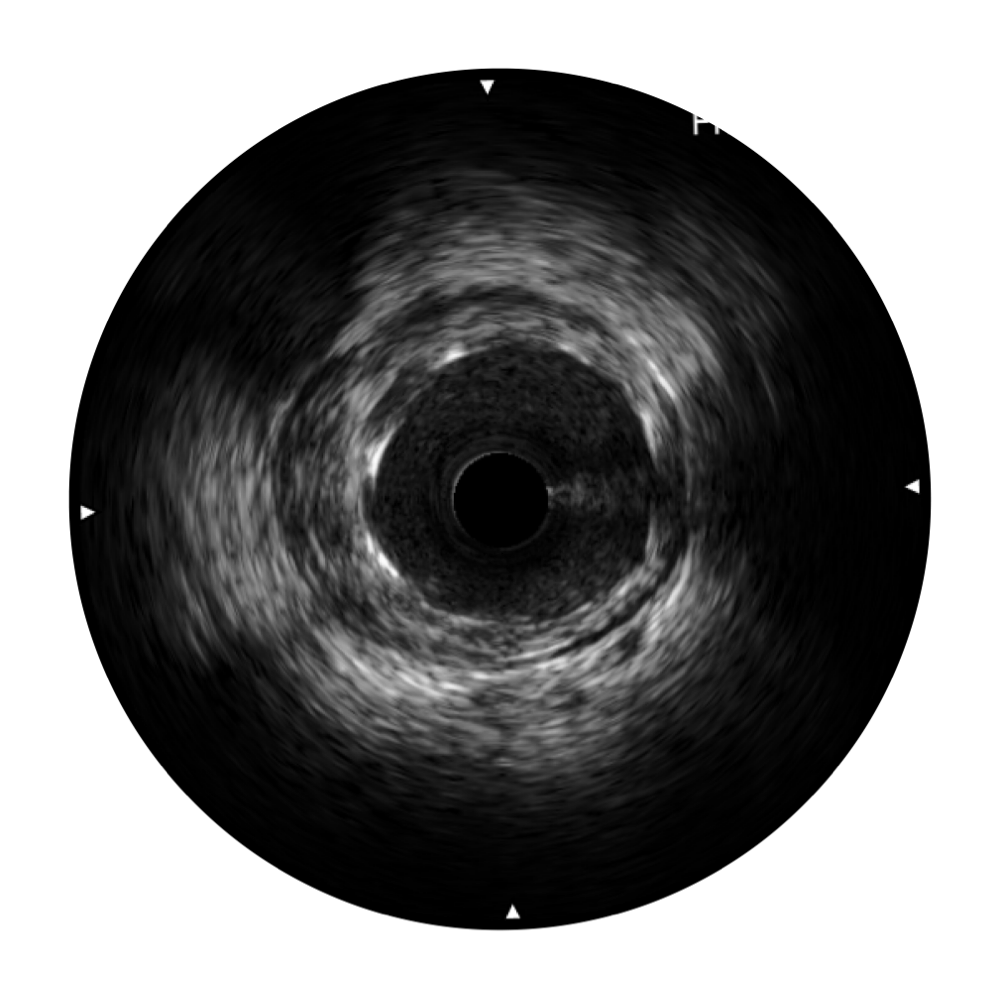

• 竞技宝(JJB)官方网站宽频IVUS图像

• 传统IVUS图像

对比传统IVUS导管成像,竞技宝(JJB)官方网站宽频IVUS图像的近场支架梁显影更细腻,远场中膜外血管仍清晰可辨,兼顾远中近,兼顾分辨力与穿透深度